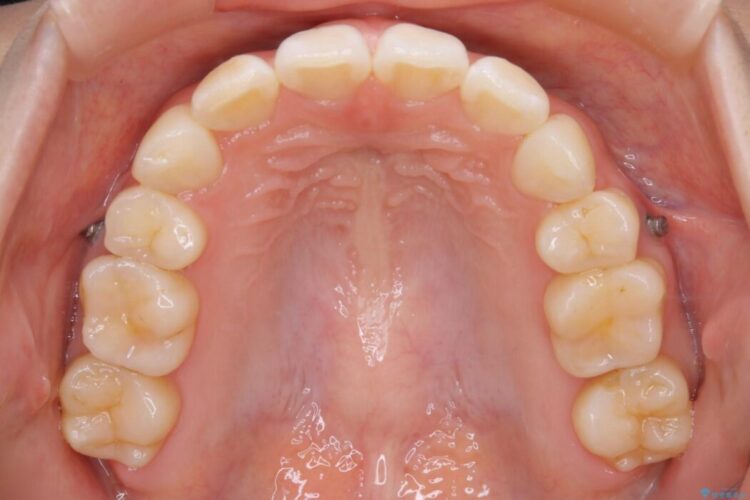

治療後について

後戻りしていた歯列もきれいに整い患者様にはご満足いただけました。

既に上下左右の4番目の歯が抜歯されているため、今回のケースでは非抜歯による歯の移動のみで矯正をしなければならず、難易度が高いものになりました。